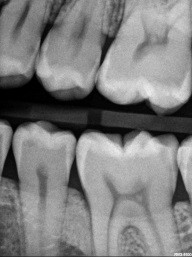

Patient 4: Teeth #12 and #13

On the black-and-white image, the patient has caries on #12, #13, #18, #19 and #20. We will focus on #12 and #13, especially the mesial of #13. The black-and-white image is less suggestive there than on #12. The photo tells a very different story. #13 is more advanced.